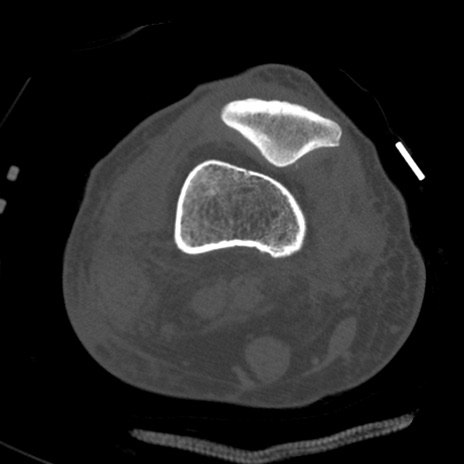

症例28 右膝関節CT(横断像)

右膝関節CT